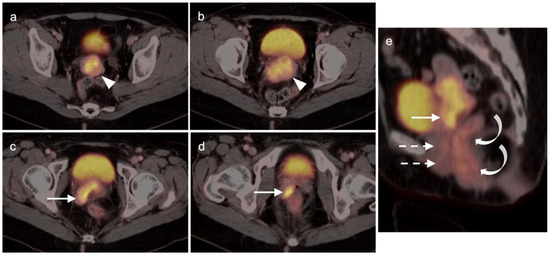

2.6. Vulvar Carcinoma